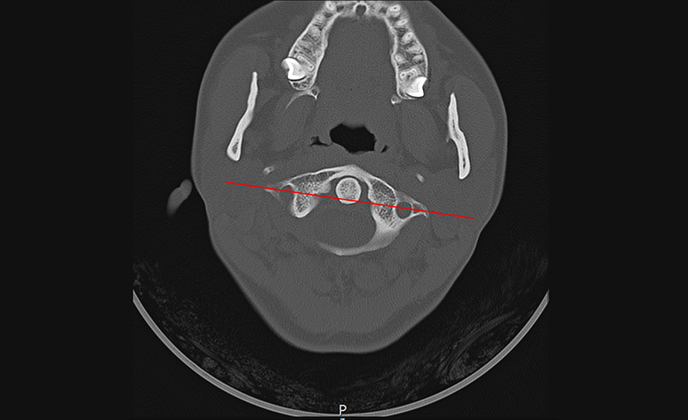

▲ 정상체혈판

▲ 치료 전 (2016년 1월 21일)

▲ CTA 5개월 착용 (2016년 6월 29일)

▲ CTA 9개월 착용 (2016년 10월 29일)